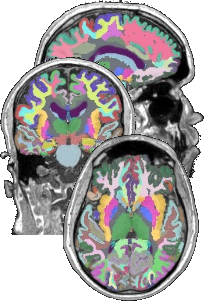

- TractQuerier (Wassermann et al. 2016)

Dictionary

Atlas

Caudate.left |= 11

Caudate.right |= 50

Putamen.right |= 51

Pallidum.right |= 52

Hippocampus.right |= 53

Amygdala.right |= 54

Insula.right |= 55Dictionary

Insula.right |= 55Queries

cc_superiotemporal =

superiortemporal.left

and superiortemporal.right

not in subcortical.left

not in subcortical.right

not in cerebellum